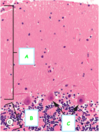

What is the structure? [1]

What has been stained brown using immunohistochemistry? [1]

A

A Lewy body (stained brown) in a brain cell of the substantia nigra in Parkinson’s disease. The brown colour is positive immunohistochemistry staining for alpha-synuclein.